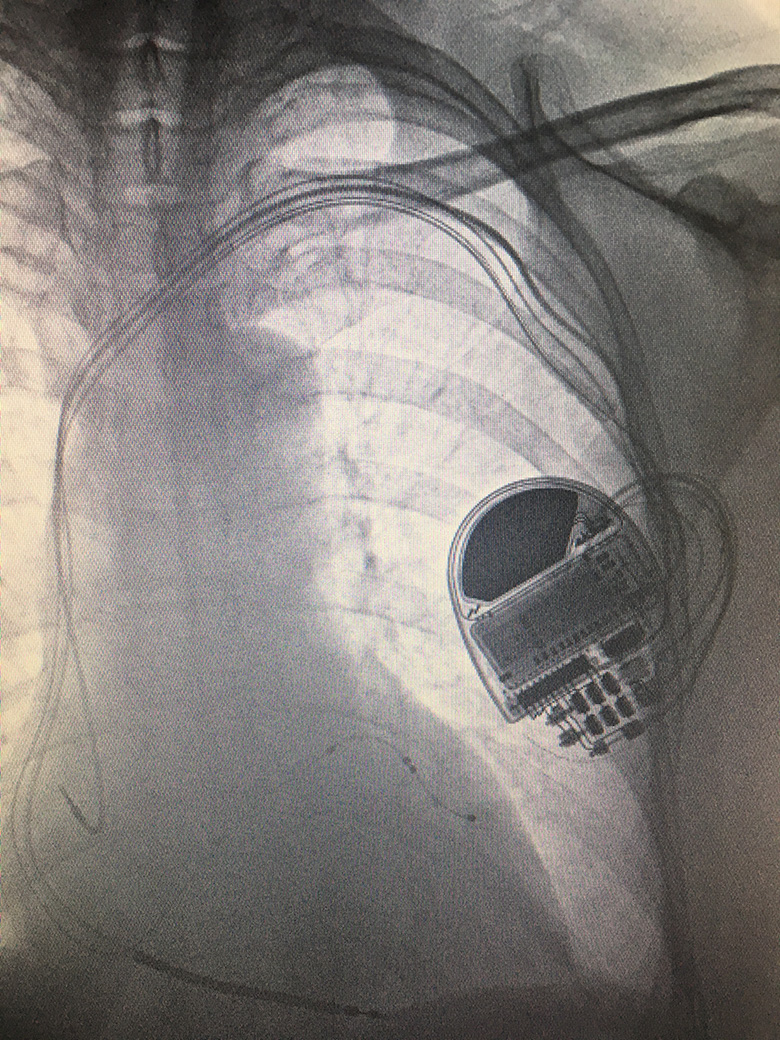

Implantable Cardioverter-Defibrillator (ICD) and cardiac resynchronisation therapy (CRT)

Patients with a known history of cardiac arrest and ventricular tachyarrhythmia, or if considered at high risk of such events, may be offered an Implantable Cardioverter-Defibrillator (ICD). An ICD device is larger than a conventional pacemaker and can be connected to an electrical defibrillator-pacing lead and, if required, a standard atrial pacemaker lead.

Selected patients with symptomatic heart failure may benefit from an additional left ventricular pacemaker lead positioned within the coronary sinus vein. This is known as cardiac resynchronisation therapy (CRT), which can improve heart function, symptoms and prognosis. CRT can be combined with an ICD, known as CRTD, or simply as a pacemaker, or CRTP.

Biventricular ICD (CRTD)

The procedure is performed by a cardiologist, under local anaesthetic and light sedation, in sterile surgical conditions. A 4-5cm incision is made on the chest wall approximately 1cm below the collar bone. The subclavian, axillary or cephalic veins located here are accessed, in the same way as a pacemaker procedure, to position electrical leads within the right ventricle, right atrium and coronary sinus vein, as required, under X-ray guidance before connecting to a ICD/CRT device.

After the device is fitted, patients usually stay overnight in hospital and undergo a chest X-ray, device check and wound review before being discharged home. Heart rhythm devices require regular long term follow up after discharge. ICD/CRT device battery life can last up to 6 years, depending on individual use and circumstances, before requiring a battery change procedure.

ICD/CRT device insertion procedures are invasive and involve permanent implants. There are small degrees of risks involved, including infection, bleeding, lead displacement, pneumothorax (puncture of the lung), tamponade (puncture of the heart), lead failure and inappropriate shocks, which would be discussed further with your specialist.